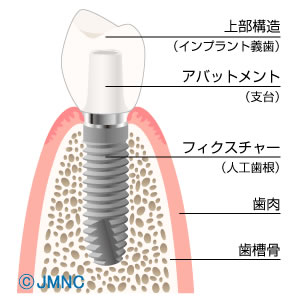

![]() インプラントなどの先端医療の紹介

インプラントなどの先端医療の紹介